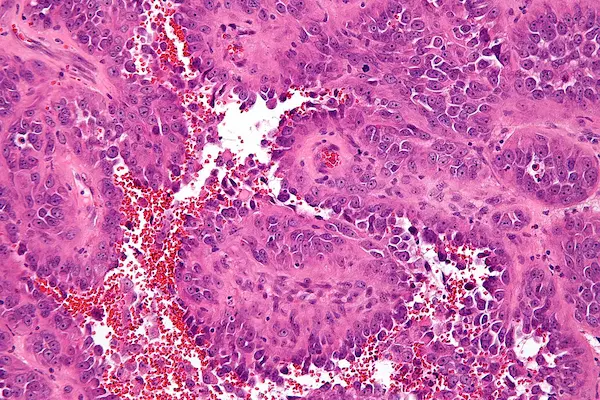

آنژیوسارکوم

آنژیوسارکوم (Angiosarcoma) نوعی سرطان نادر است که از سلول‌های اندوتلیال تشکیل می‌شود. سلول‌های اندوتلیال سلول‌هایی هستند که سطح داخلی رگ‌های خونی و لنفاوی را پوشانده‌اند. آنژیوسارکوما می‌تواند در هر نقطه از بدن ایجاد شود، اما بیشتر در اندام‌های بزرگ مانند کبد، طحال، ریه‌ها و قلب دیده می شود. این بیماری همچنین می‌تواند در استخوان‌ها، پوست و بافت‌های نرم یافت شود. علت آنژیوسارکوما ناشناخته است، اما برخی از عوامل ممکن است خطر ابتلا به این بیماری را افزایش دهند، از جمله:

• بیوپسی: در بیوپسی، نمونه کوچکی از بافت تومور برداشته و برای بررسی زیر میکروسکوپ به آزمایشگاه فرستاده می‌شود.